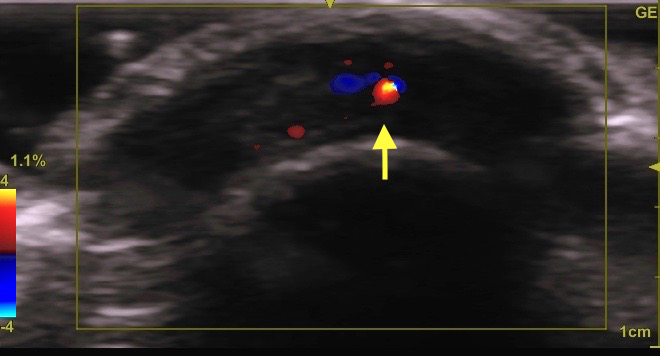

こういった場合は、小さく切開して中身を出してから、

後日切除する方が、小さな傷口で済みます

その時は、開口部(→)で切開することが肝要です。

下写真のケースの場合は、矢印の所が開口部です。

右写真のエコーで確認できます(→)。その下に本体がいます。